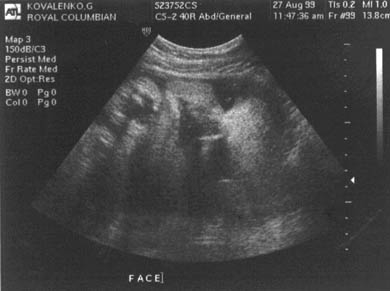

УЗИ на 42 неделе беременности

Ультразвуковое исследование позволяет определить необходимость в искусственной стимуляции родов. К опасным признакам относятся:

-

наличие мекония в околоплодных водах;

нарушения в работе плаценты;

недостаточный объем амниотической жидкости.

На ультразвуковом исследовании плод выглядит как полностью развитый новорожденный.

Фото УЗИ на 42 неделе беременности